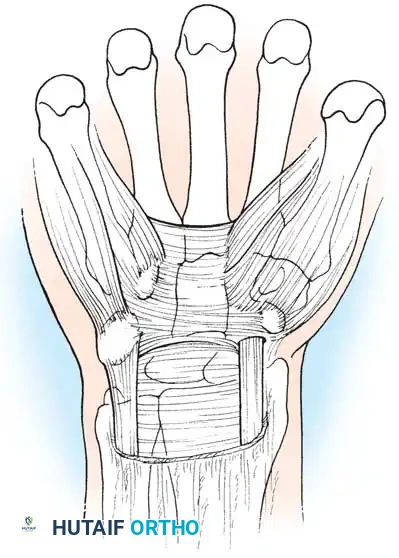

Step 2: Superficial Dissection

The skin and subcutaneous fat are incised. The palmar aponeurosis is identified and longitudinally divided. Care is taken to stay strictly ulnar to the longitudinal axis of the palmaris longus to protect the Palmar Cutaneous Branch of the Median Nerve (PCBMN).

Figure 10: Superficial dissection highlighting the palmar fascia. The PCBMN lies radially and must be protected.

Step 3: Division of the Transverse Carpal Ligament

The distal edge of the TCL is identified. Using a scalpel or specialized scissors, the TCL is divided longitudinally along its extreme ulnar border. Releasing the ligament on the ulnar side prevents injury to the median nerve and its recurrent motor branch.

Figure 11: Initial division of the transverse carpal ligament.

Figure 12: Complete longitudinal division of the TCL, exposing the underlying median nerve and flexor tenosynovium.